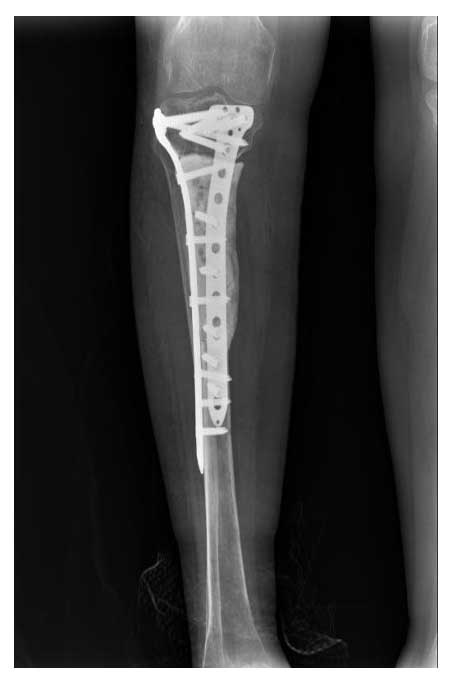

Görsel Açıklamaları

Ameliyat Sonrası: Röntgende tümörün temizlenmesi sonrası oluşan boşluğun kemik çimentosu ile doldurulması ve iki adet anatomik plak ile güçlendirilmesi görülmekte.